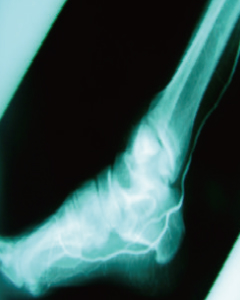

버거씨병

Buerger’s Disease-

Before

-

줄기세포 치료 30일 후

줄기세포 치료 120일 후

- 하지 혈류 개선

- 치료 후 종아리 근육부위에 새로운 혈관이 형성되었고 혈류의 흐름이 호전되었습니다.

- 족부 혈류 개선

- 치료 후 종아리 족부에 새로운 혈관이 형성되었고 혈류의 흐름이 호전되었습니다.